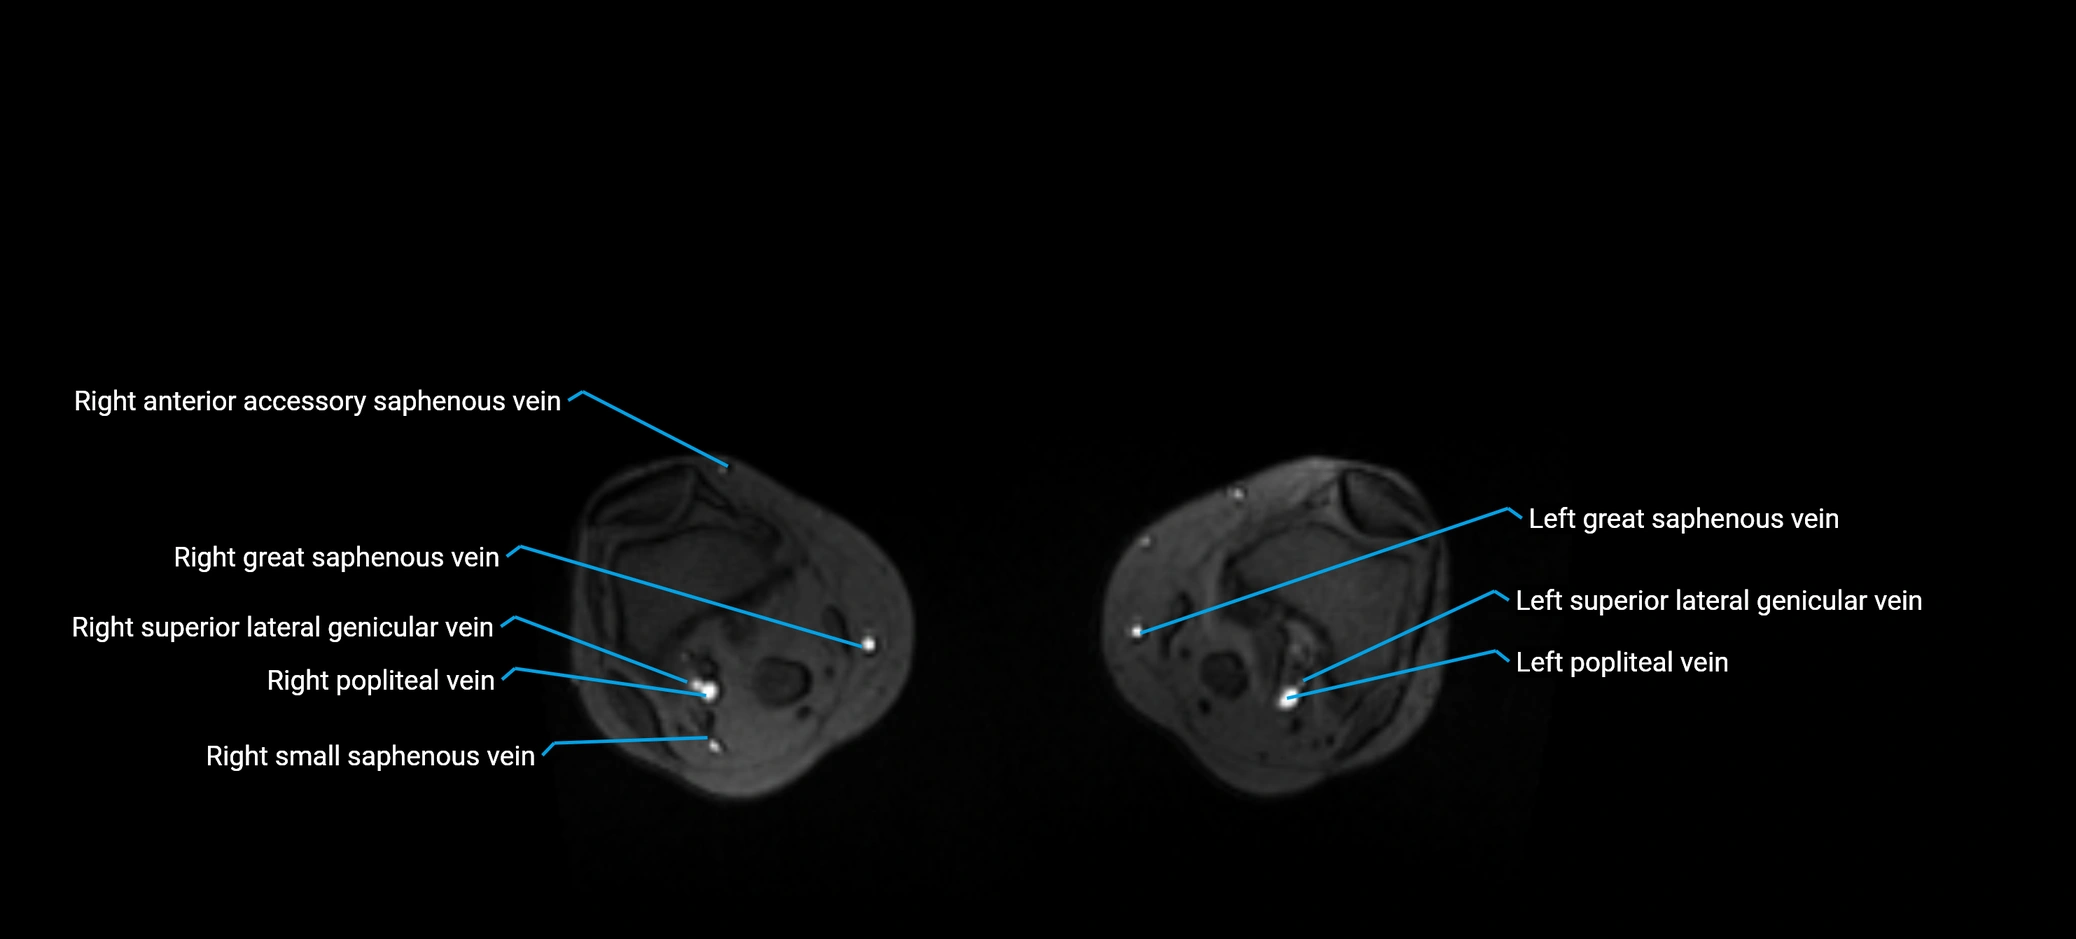

MRI image

image